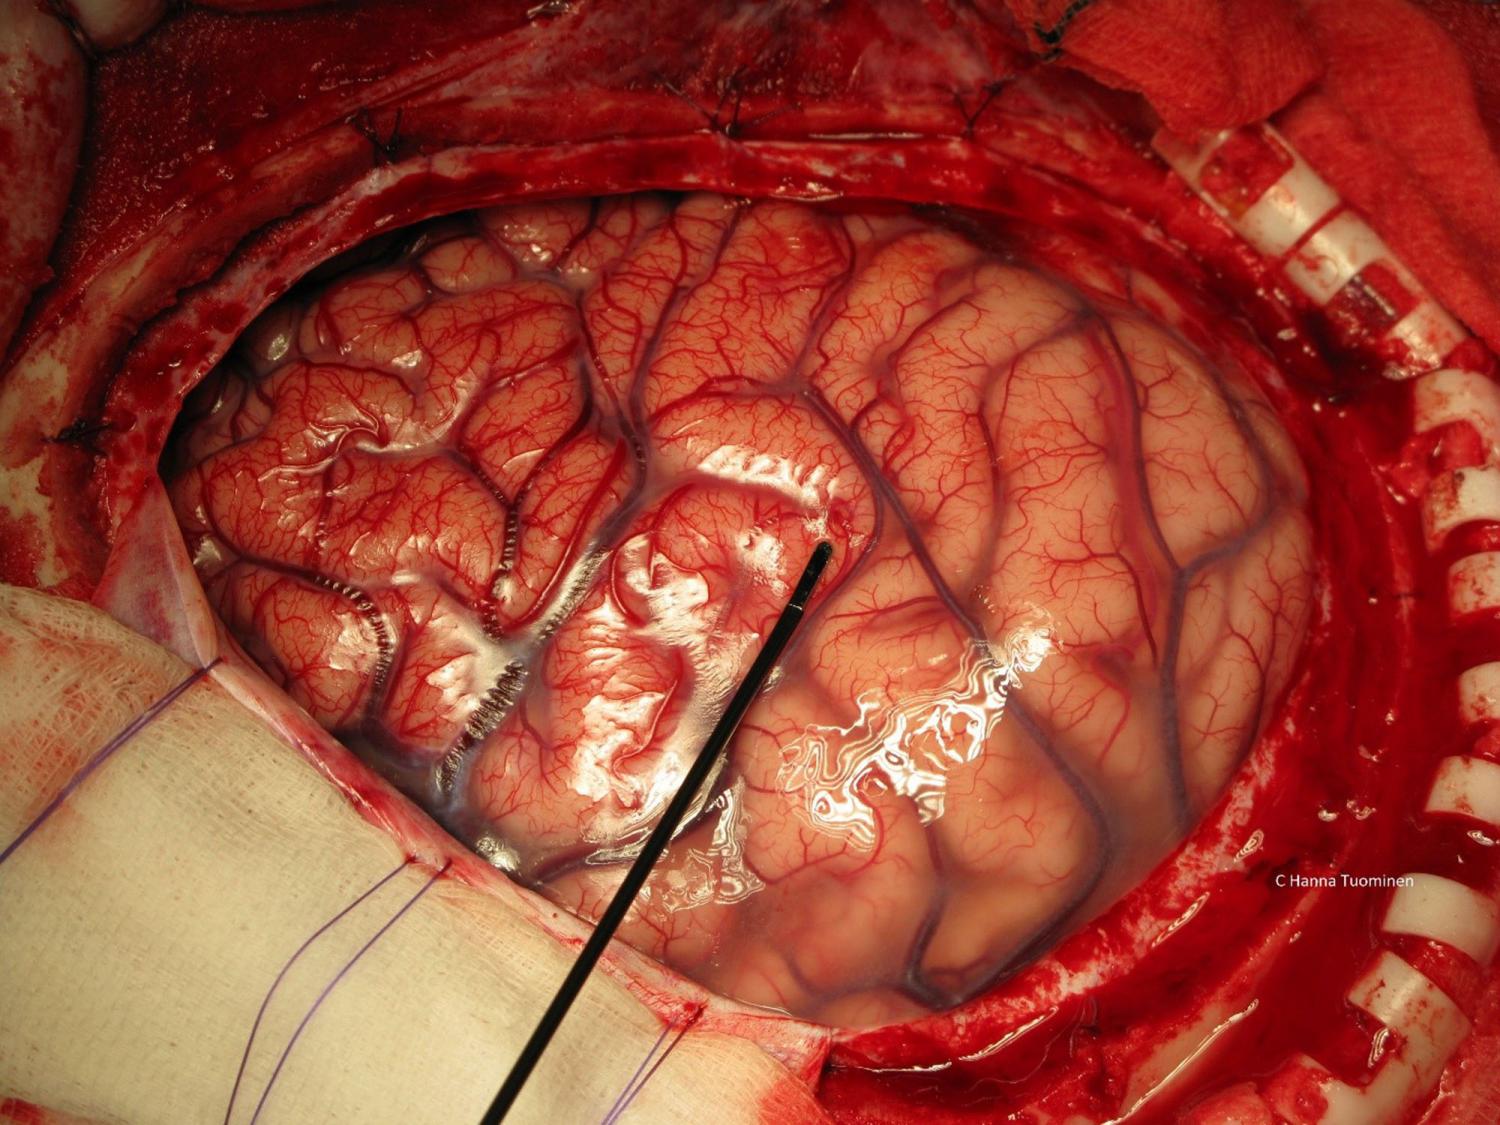

‘Tumours like this grow into the brain instead of displacing it, the tumour cells pushing into the brain’s soft substance, weaving their way between the nerve fibres and the brain cells of grey matter. The brain can go on working for a while even though the tumour cells are boring into it like deathwatch beetles in a timber building, but eventually, just as the building must collapse, so must the brain.’

One silver lining to Marsh’s book is that you learn that some famously intimidating tumours can be benign. The huge golf-ball tumour that appears on brain scans in TV serials and films is often not the short straw in the realm of brain tumours. These tumours are mostly external to the brain which essentially sit on it and decompress it – they displace the brain, which can cause death from excess pressure. These however can be removed and the patient can make a full recovery. The tumour to fear is one that will appear on a scan like a dark smudge. This is invasive and may alter everything from your personality to your vital senses before killing you. These tumours are therefore much harder to treat, and removal involves careful manoeuvring around critical brain tissue. Marsh’s accounts of these surgeries are often harrowing.